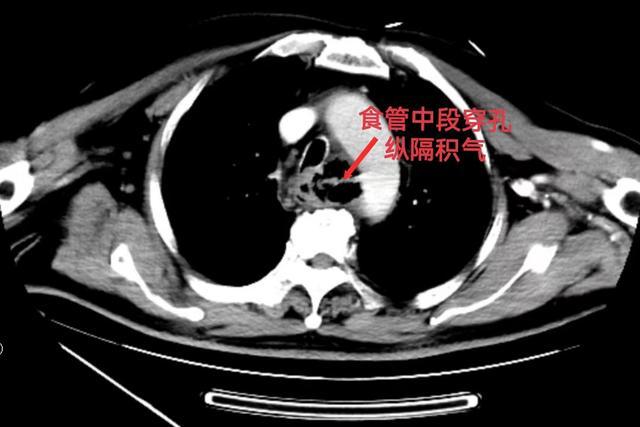

急诊CT检查提示:食管中段穿孔并纵膈积气,食管内不规则等密度灶,外缘紧贴主动脉弓右侧壁。考虑食道异物损伤、食管破裂导致纵隔感染。因未见骨头异物,暂时予以止痛、护胃、抗感染等治疗,准备有条件再做胃镜进一步明确诊断。